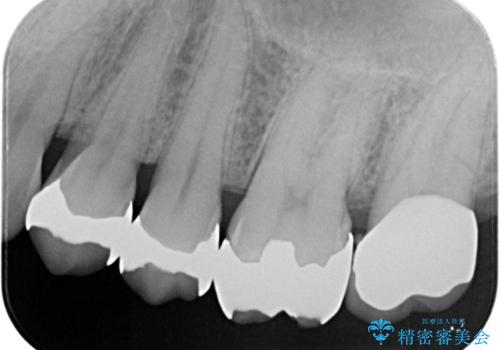

- 主訴:詰め物と歯の境目に穴が空いているとクリーニング時衛生士から指摘された。

保険適用のメタルインレー歯質の境目が虫歯になっていたため、一度メタルインレーを除去し虫歯の範囲の把握と補綴物のやり替えをお勧めし、ジルコニアクラウンでのやり替えとなりました。

保険適用のメタルインレーと歯質の境目にう窩ができており、補綴物のやり替えとなりなした。